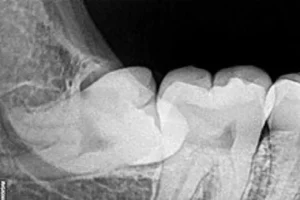

In medicine, wisdom teeth are also called third molars. They are the eighth teeth from front to back. Wisdom teeth are the last permanent

There are 32 teeth in the human permanent dentition, of which the last four third molars are located at the back of the upper,